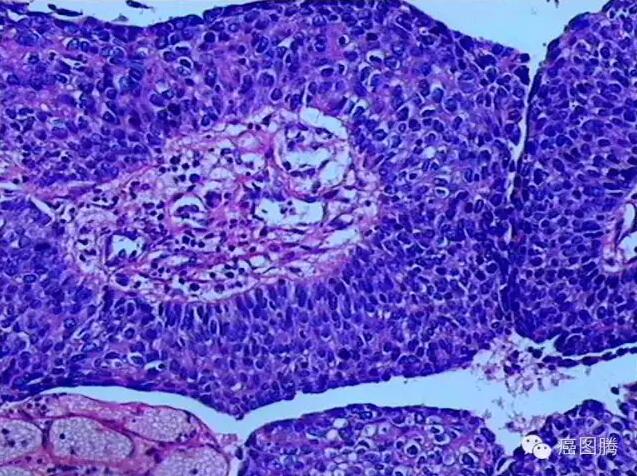

也可称为再生或新生(neogenesis),是指为修复缺损而发生的同种细胞的增生。炎症、再生、代偿等可引起组织细胞新生,本质上是为了修复缺损,而不是为了吸收坏死物质或消除致炎因子,再生的细胞与缺损的实质细胞完全相同。淋巴细胞新生对淋巴细胞白血病发生,血管新生对恶性实体肿瘤的生长、转移乃至预后都有着极其重要的意义。新生可发生于皮肤或粘膜表面的鳞状上皮,也可发生于腺上皮。上皮细胞异乎常态的增生,表现为增生的细胞大小不一,形态多样,核大而浓染,核浆比例增大,核分裂可增多但多呈正常核分裂像。细胞排列较乱,细胞层次增多,极向消失,但一般不见病理性核分裂;细胞增生从良性改变到恶性改变的中间站,是由量变到质变的关键点,因此,将非典型增生称之为“癌前病变”。